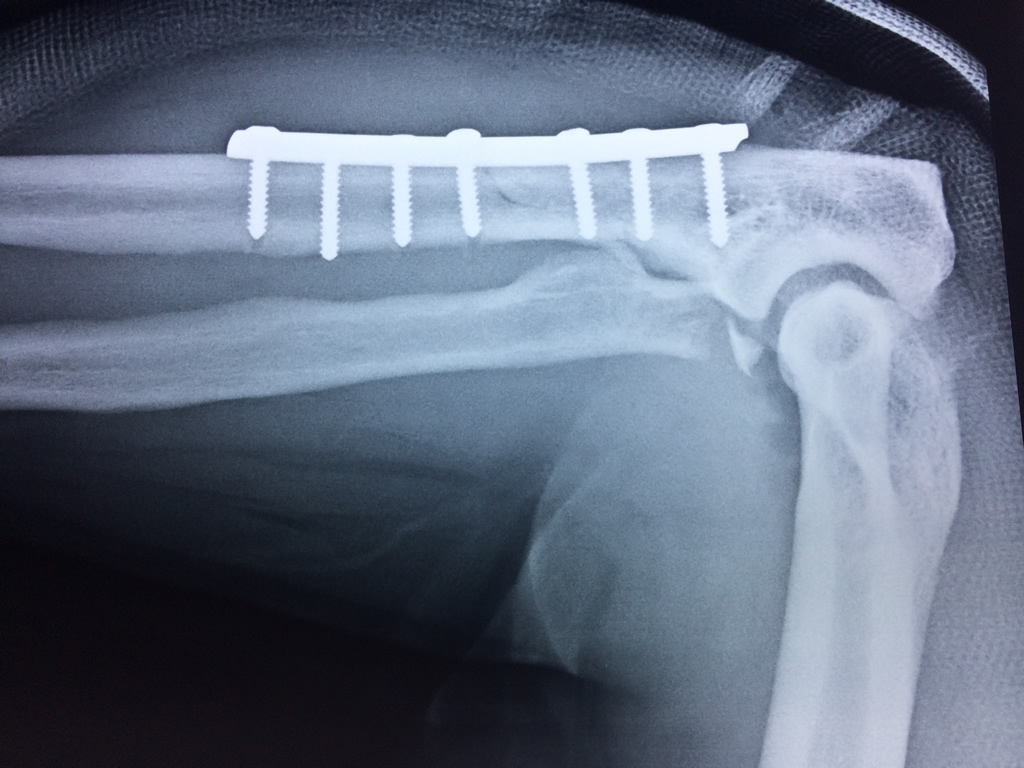

En anatomía humana, la articulación del codo es la que une el brazo con el antebrazo, conectando la parte distal del hueso húmero con los extremos proximales de los huesos cúbito y radio.

La articulación principal que constituye el codo se denomina humero radio-cubital y puede dividirse en dos partes bien diferenciadas, la articulación humero-radial y la humero-cubital.